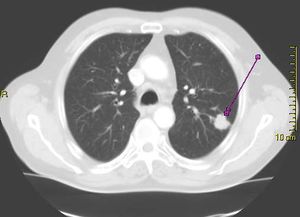

- الأشعة السينية

- مسح مقطعي (الأشعة المقطعية)